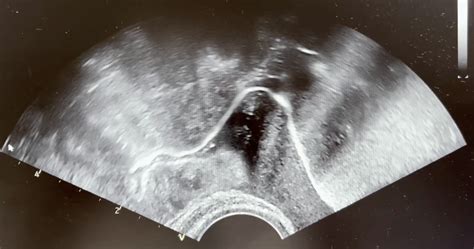

- Ultrazvočno spremljanje: Med vbrizgavanjem kontrasta ginekolog s transvaginalnim ultrazvokom spremlja potovanje kontrastnega sredstva skozi maternico in jajcevode. Če so jajcevodi prehodni, kontrast skozenj nemoteno teče in izstopi v trebušno votlino, kar je jasno vidno na ultrazvočnem zaslonu. Če pride do zapore, se kontrast nabere pred njo ali pa sploh ne preide skozi.

Hysterosalpingo-contrast-ultrasonography (HyCoSy)